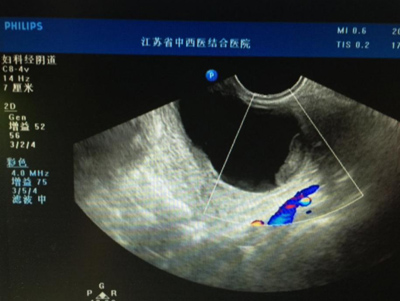

另一类卵巢囊肿是带颜色的,因其囊液的颜色是棕褐色,因此我们又称之为“巧克力囊肿”,也就是卵巢子宫内膜异位囊肿,多见于生育年龄女性,发病率约占育龄妇女的15%左右。与之前的生理性囊肿不同,一般患者有经期腹痛、不孕症病史,但有些人也没有任何症状,体检时偶然发现。这部分女性往往因CA125升高而产生心理的紧张情绪,但一般数值不超过200单位。CA125是一种“肿瘤”抗原,是一位美国医生首先发现可用于卵巢癌的诊断,但后来人们发现在盆腔炎症、卵巢子宫内膜异位囊肿、盆腔结核等情况下,也会出现不同程度的升高。那么“巧克力囊肿”需要手术治疗么?因为多数患者合并不孕,且卵巢子宫内膜异位囊肿有一定的恶病率,所以我们建议可以选择手术治疗,当然也可以根据患者的症状和囊肿的大小等情况,选择药物治疗或观察。